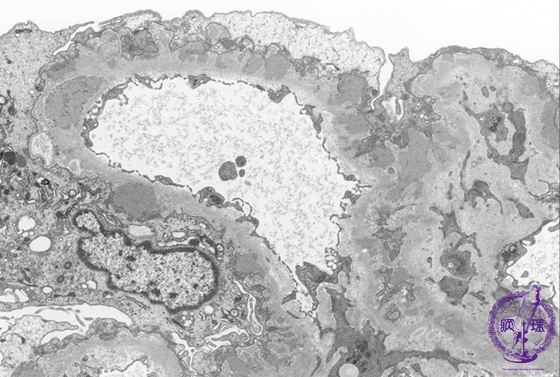

- ★(2)Membranous nephropathy

Electron microscopic findings: Stage II (focally Stage III). The number and size of electron dense subepithelial deposits (red arrows) are increased and spikes are seen forming between deposits (dotted blue line).